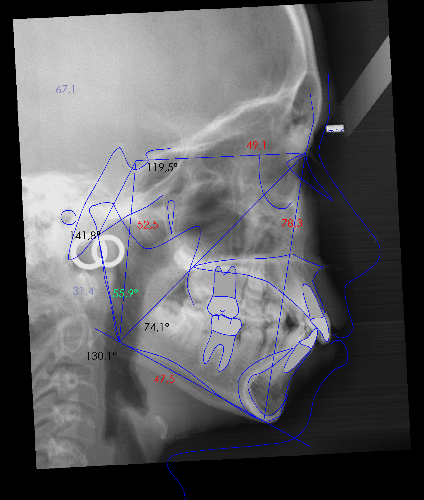

La paciente O.O. acude a nuestra consulta por:

– Canino 13 e incisivo lateral 42 en posición ectópica.

– Canino 23 incluido.

Con lo que decide realizarse un tratamiento de ortodoncia de duración de 24 meses con brackets damon Q.

CASO COMPLETO: